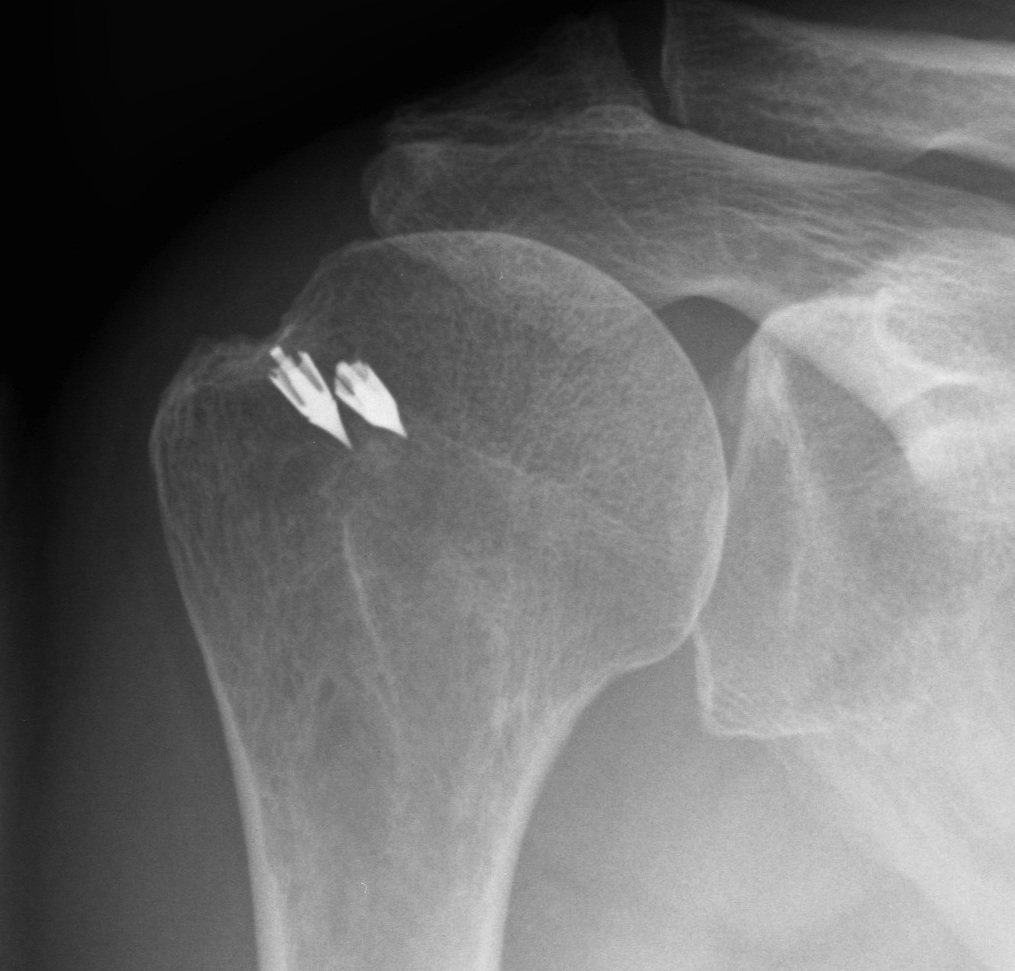

Repair techniques

Transosseous

- with open repair

- pass cuff sutures through drill holes in bone

Single row anchor

- insert anchors at lateral edge of footprint

Double row anchors

- medial anchor row at articular margin and tie through medial cuff

- lateral anchor row at lateral footprint used to secure sutures

- increase surface area of cuff repaired to foot print

Trans-osseous equivalent / suture bridge

- cross sutures from medial row to lateral row

- increase contact between cuff and footprint